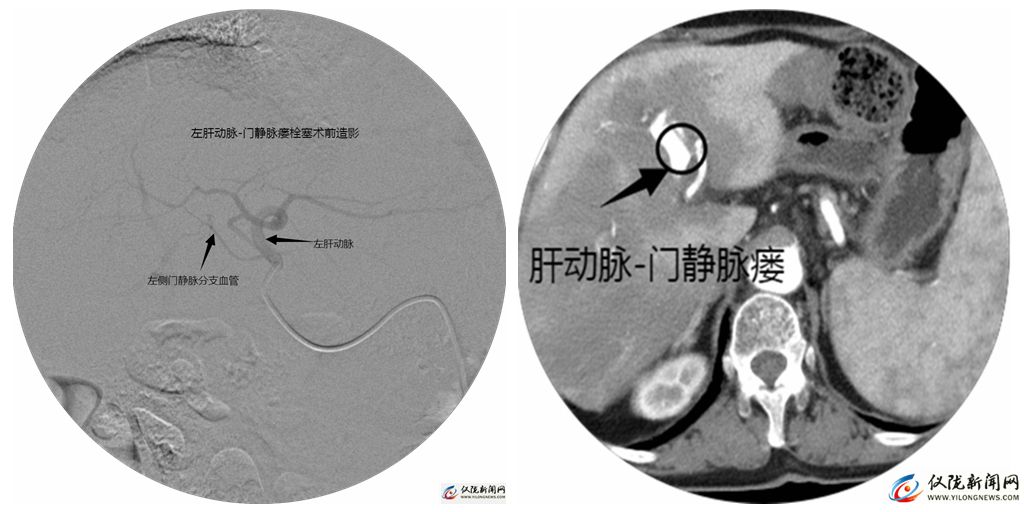

此次,患者拟行食管胃底静脉曲张介入治疗再次入院,入院后主管医师行术前评估。完善腹部增强CT及CTA检查后,消化内科及放射科进行联合讨论,发现患者肝硬化影像学特征不典型,结合患者腹部CTA及相关辅助检查结果,考虑患者门静脉高压原因并非是常见的肝硬化所致,而是一种少见疾病,即肝功脉-门静脉瘘所致。据此,医院确定放射介入治疗为优选方案。

左图为栓塞术前造影

右图栓塞术前CT